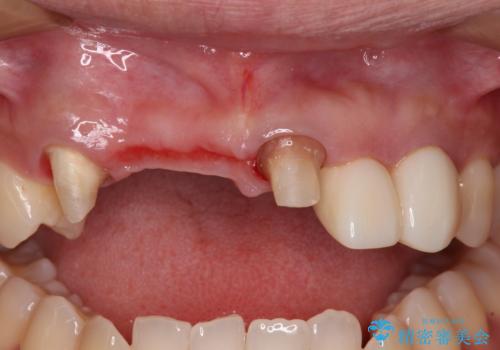

抜歯後には歯を支えていた骨が失われるため、歯肉が痩せてしまい、結果としてブリッジのダミーの歯を長くする必要があります。

歯肉が痩せてしまっている状態を改善するため、口蓋から歯肉の結合組織を採取し、移植することで厚みを増大させることとし、その後オールセラミックブリッジにて補綴治療を行うこととしました。